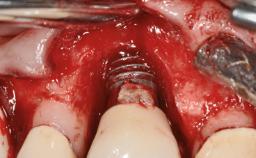

In 2004, the patient, a smoker, began dental treatment at the ACTA graduate clinic. She was a TV producer exposed to a lot of stress in her job and had a sick husband. Her maxillary teeth had been extracted, as had the mandibular canines, premolars, and molars, with the exception of tooth 34. She received a complete maxillary denture and a mandibular skeleton denture. In October 2007, her maxilla was augmented by an oral and maxillofacial surgeon; in March 2008, implants (Biomet 3i, Palm Beach, Florida, USA) were inserted at that same clinic. In 2008, the patient was presented at the Department of Oral Implantology and Prosthetic Dentistry to request restorations for her implants. An implant-supported overdenture was planned. She also asked if we could restore her occlusion with fixed prosthetics.